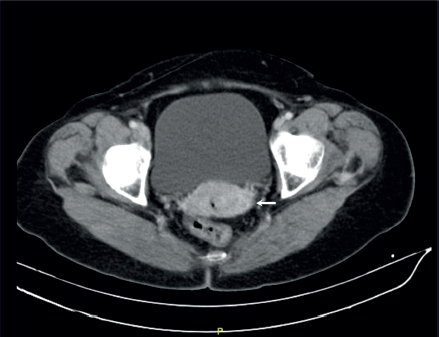

With such results, she was referred to the National Institute of Neoplastic Diseases – Lima, Peru and in August 2015 was admitted to the Department of Gynecologic Oncology, being approached integrally and the physical examination found normal external genitalia, wide elastic vagina without lesions, in the cervix was observed exophytic tumour, bleeding, stony, mobile, irregular predominantly in the posterior lip with proliferative lesion extending to the posterior cul-de-sac measuring 3.8 × 3 cm. Digitorectal examination: Parametrium not compromised by neoplasia. It is complemented with imaging studies: Tomography 22.08.2015: Tumour-like cervix measuring 4 cm in transverse diameter, there is associated alteration of the adjacent fatty planes. There is no evidence of retroperitoneal adenopathy in the iliac, mesenteric or inguinal chains. No signs of hydronephrosis. There is no evidence of free liquid in the abdomino-pelvic cavity. Bone structures without lytic or blastic lesions are evident. Soft tissues without alterations (Figure 1).

Figure 1. Abdominal and pelvic tomography with contrast, coronal section. There is contrast-enhancing tumour formation predominantly in the lower lip of the cervix of 4 cm (arrow), there is no involvement of the parametria or adenopathies suggestive of secondary involvement.